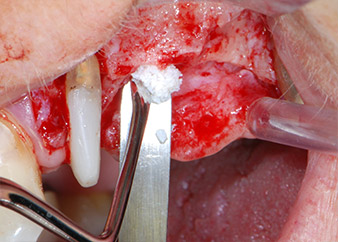

IImplant beds were prepared at sites 25 and 26 with rotary instruments, used in a contra-angle handpiece with a 20 : 1 transmission ratio with an updated powerful implant motor (Implantmed, W&H) (Fig. 8).

Fig. 8: Rotary preparation of the implant bed short of the floor of the maxillary sinus at position 25, carried out with an updated implant motor.

The final preparation next to the sinus was again carried out with a piezoelectric instrument (Piezomed, insert S2).

Prior to implant placement, and following verification of an intact Schneiderian membrane (Fig. 9), the internal sinus floor was augmented at both implant sites by means of xenogeneic bone substitute material (Bio-Oss, Geistlich Biomaterials) (Fig. 10).

Fig. 10: Introduction of xenogeneic bone substitute material into the implant osteotomy for internal sinus augmentation. The material was carefully condensed in an apical direction with the ball-ended CPITN probe (not shown).